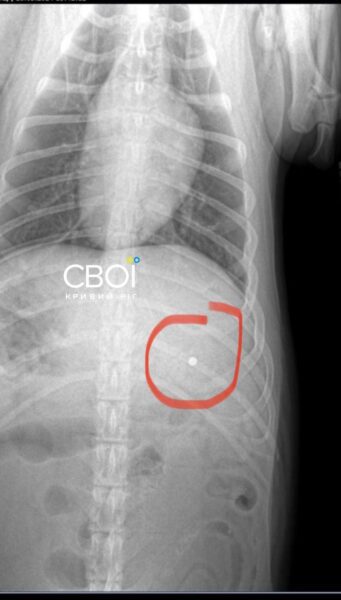

Ветеринар назначил лечение для Бати. Одна из пуль застряла в голове животного, другая — возле желудка. Достать их, чтобы не навредить собаке, невозможно.